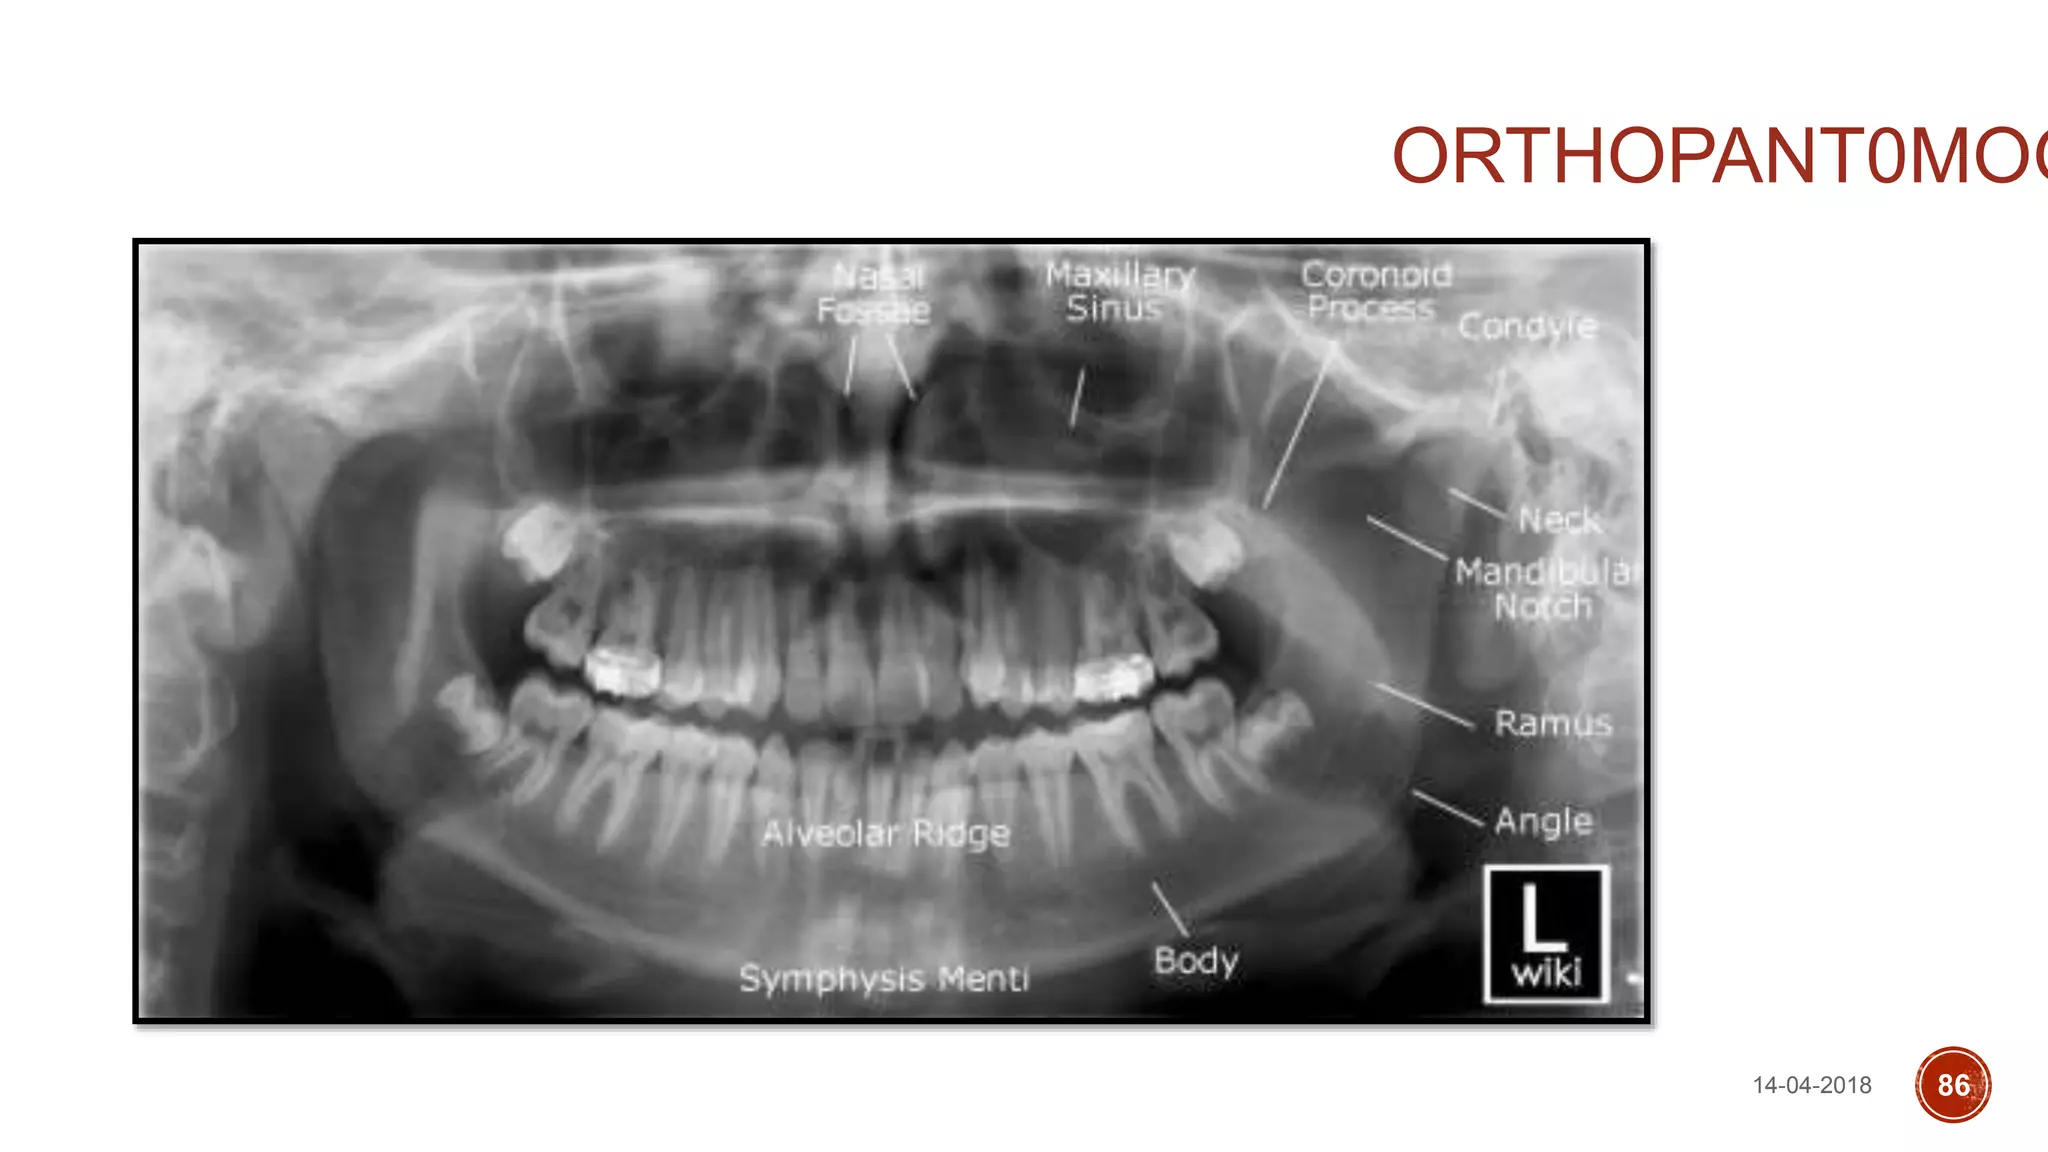

ORTHOPANTAMOGRAPH (OPG)

ORTHOPANT0MOG

14-04-2018 86